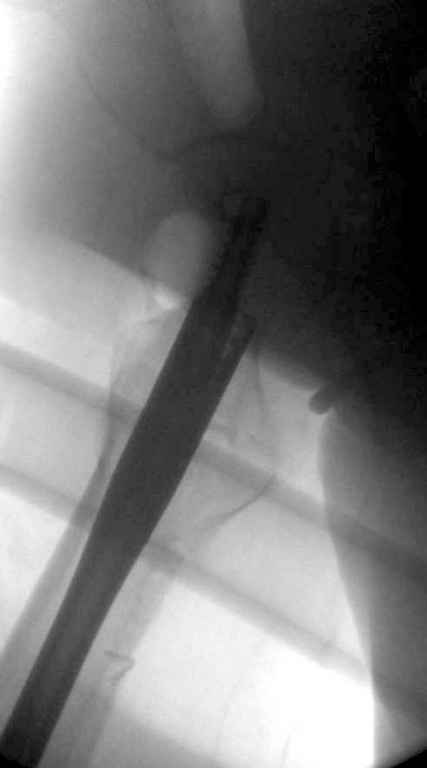

Вашему вниманию представляется похожий случай, пациентке 70, осложнился в течение одного месяца после операции. Ревизия с заменой сустава, кабельная фиксация на трохантер. При установке в дистальном диафизе обнаружен тонкий кортикальный слой и сделана профилактика от возможного перелома аллографтом.

В данном случае в головке бедра и в вертлужной впадине огромный дефект, навряд ли удалением импланта или заменой на другой можно сохранить сустав.